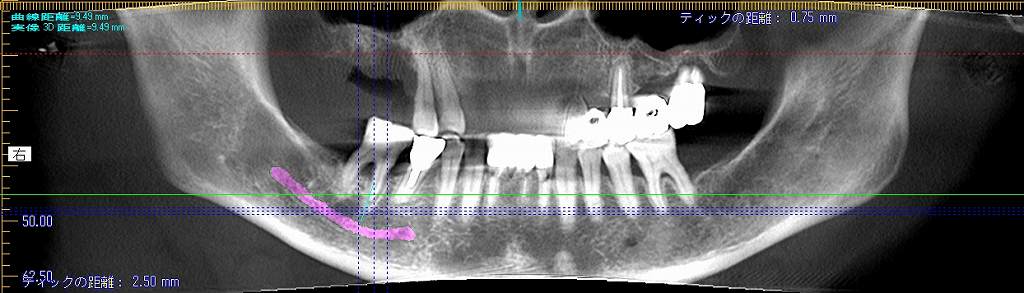

術前のパノラマになります

臼歯部での咬合のサポートが欠落していました

コンタクトも1㎜すいてきました

物がよく挟まるそうです

このように5㎜の13㎜というインプラントを埋入しています

隙間には像骨処置として骨補填材を敷き詰めています

術前と術後のパノラマになります